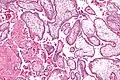

Micrograph showing chorionic villi. Intermediate magnification. H&E stain. -